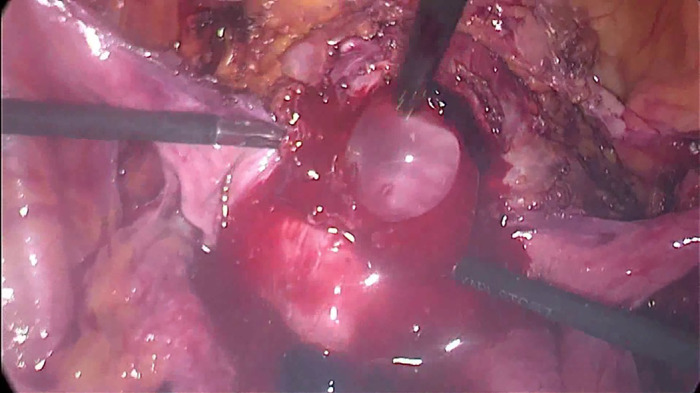

Intervention: The video presents a systematic approach of the laparoscopic treatment of CSP clearly divided into 10 steps: 1. Prepare the surgery; 2. Inspection of the pelvis; 3. Bladder dissection; 4. Preventive haemostasis; 5. Hysterotomy; 6. Evacuation of conception products; 7. Excision of niche scar tissue; 8. Evacuation of the uterine cavity; 9. Suturing of the uterine defect; 10. Removal of the uterine artery clips. The main outcome measures are the efficacy of the laparoscopic management of CSP and the postoperative uterine reconstruction in terms of ultrasonic measurement of the isthmic myometrial layer thickness. Patients are released from the hospital the day after the surgery, and a follow-up ultrasound is scheduled three months post-operatively. In the case presented in the video, the myometrial wall is increased from 3 mm preoperatively to 13 mm three months postoperatively.

Conclusions: The main advantage of this technique is the ability to treat CSP, remove the uterine isthmocele, and reconstruct the lower uterine segment simultaneously. The 10 steps proposed in a logical sequence may shorten the surgery's learning curve and reduce possible complications.